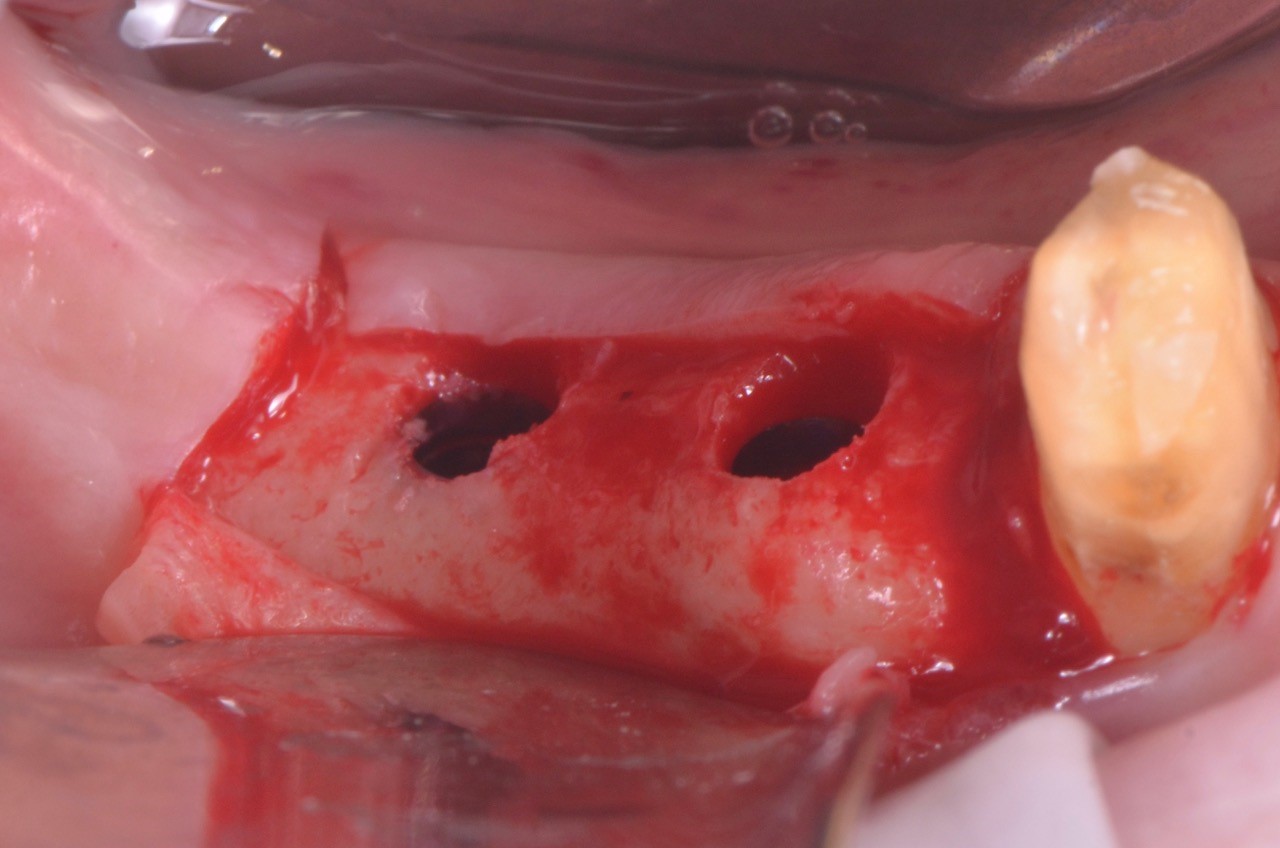

impianto-sottocrestale

Foto: impianto sottocrestale